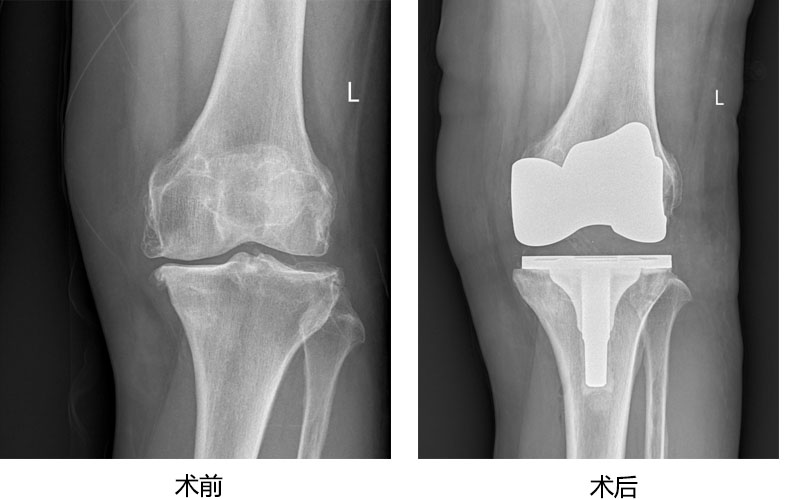

人工关节置换为广大高龄老年股骨颈骨折、股骨粗隆间骨折病人提供快速康复治疗,为严重股骨头坏死、膝关节炎病人解除病痛,恢复正常行走功能。 病例展示如下:

老年膝骨性关节炎人工膝关节置换术